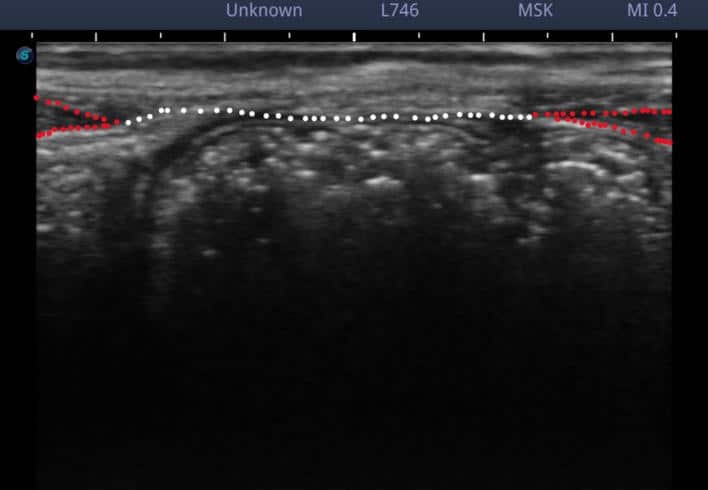

見やすくするために、マーキングしますと、

赤:腹直筋

白:白線

腹直筋離開のエコー写真

腹直筋の間にある白線が、延長しており、薄くなっているのが観察されます。